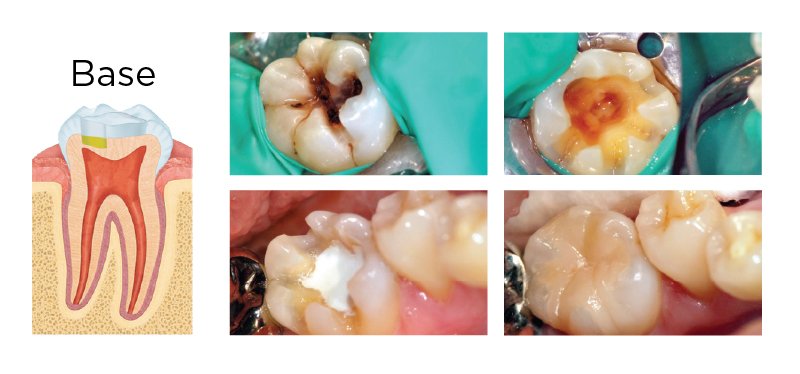

1. Coiffage Dentinaire (Indirect)

Définition

Opération consistant à placer sur une plaie vive de dentine une substance capable de permettre une guérison accompagnée d’une formation de dentine réactionnelle.

Indications thérapeutiques

• Caries à évolution rapide non pénétrantes ; lorsque l’épaisseur de dentine juxta-pulpaire résiduelle après éviction carieuse complète est inférieure à 0,5 mm (Smith, 2002)

Mise en Œuvre Clinique — Étape par Étape

1. Vérification de la vitalité pulpaire par les tests adéquats

2. Radiographie préopératoire (non indispensable mais recommandée)

3. Anesthésie : déterminée par le degré de sensibilité de la dentine

4. Mise en place du champ opératoire (digue)

5. Curetage dentinaire complet

6. Séchage à l’air tiède

7. Désinfection (peut être inutile si le produit de coiffage a des propriétés antiseptiques)

8. Pose du produit de coiffage : apposé en fond de cavité sur une épaisseur de 2 à 3 mm

9. Reconstitution provisoire de la dent : obturation coronaire provisoire étanche (ciment à base d’oxyde de zinc-eugénol, CVI, ou Biodentine®)

10. Durée de coiffage : minimum 6 semaines

Résultat et Pronostic

Le matériau de protection dentino-pulpaire (MTA ou hydroxyde de calcium) libère des ions Ca²⁺ qui passent par les tubulis dentinaires jusqu’à la pulpe. Cette augmentation de la concentration extracellulaire de calcium induit la sécrétion de fibronectine par les cellules pulpaires, réservoir de facteurs de croissance, déterminant la différenciation des néoodontoblastes et la production de dentine tertiaire (Graham et coll., 2006). Le MTA est le plus indiqué pour les coiffages pulpaires indirects pour sa stabilité à long terme.